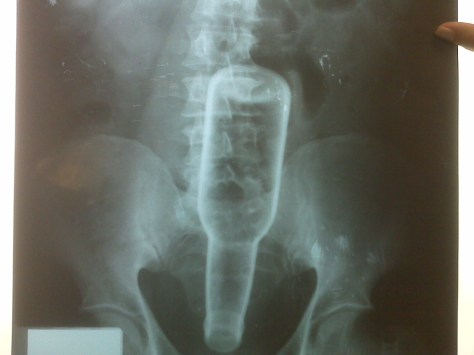

Embotellamiento

...Pues empalamiento no es.

...Pues.....................empalamiento no es.

Cuando uno ve este tipo de imagenes lo primero que se viene a la mente es pensar que es un fotomontaje, pues dejenme decirles que ojala asi fuera… si, ojala fuera un fotomontaje.

Dios mio debes esar diciendo en este momento.

Es un paciente masculino, de no se cuantos años de edad, que pues llego con un embotellamiento rectal, con posible desgarramiento interno (y muy probable de esfinter anal).